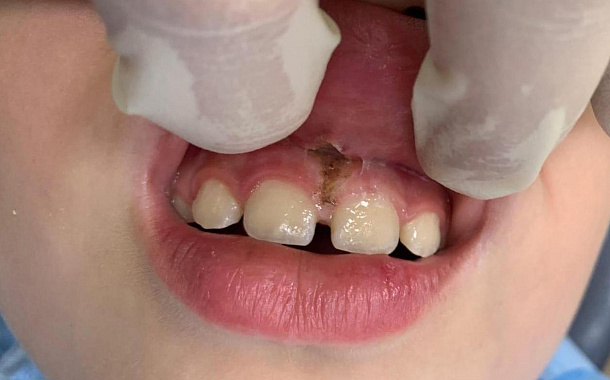

Удаление зуба с имплантацией

Пациент 22 года обратилась к терапевту с жалобами на дискомфорт при накусывании на зуб в верхней челюсти.

Диагностика показала трещину в корне зуба. Сохранить или вылечить зуб невозможно, поэтому было рекомендовано удаление зуба с последующей имплантацией.

Узнать подробнее